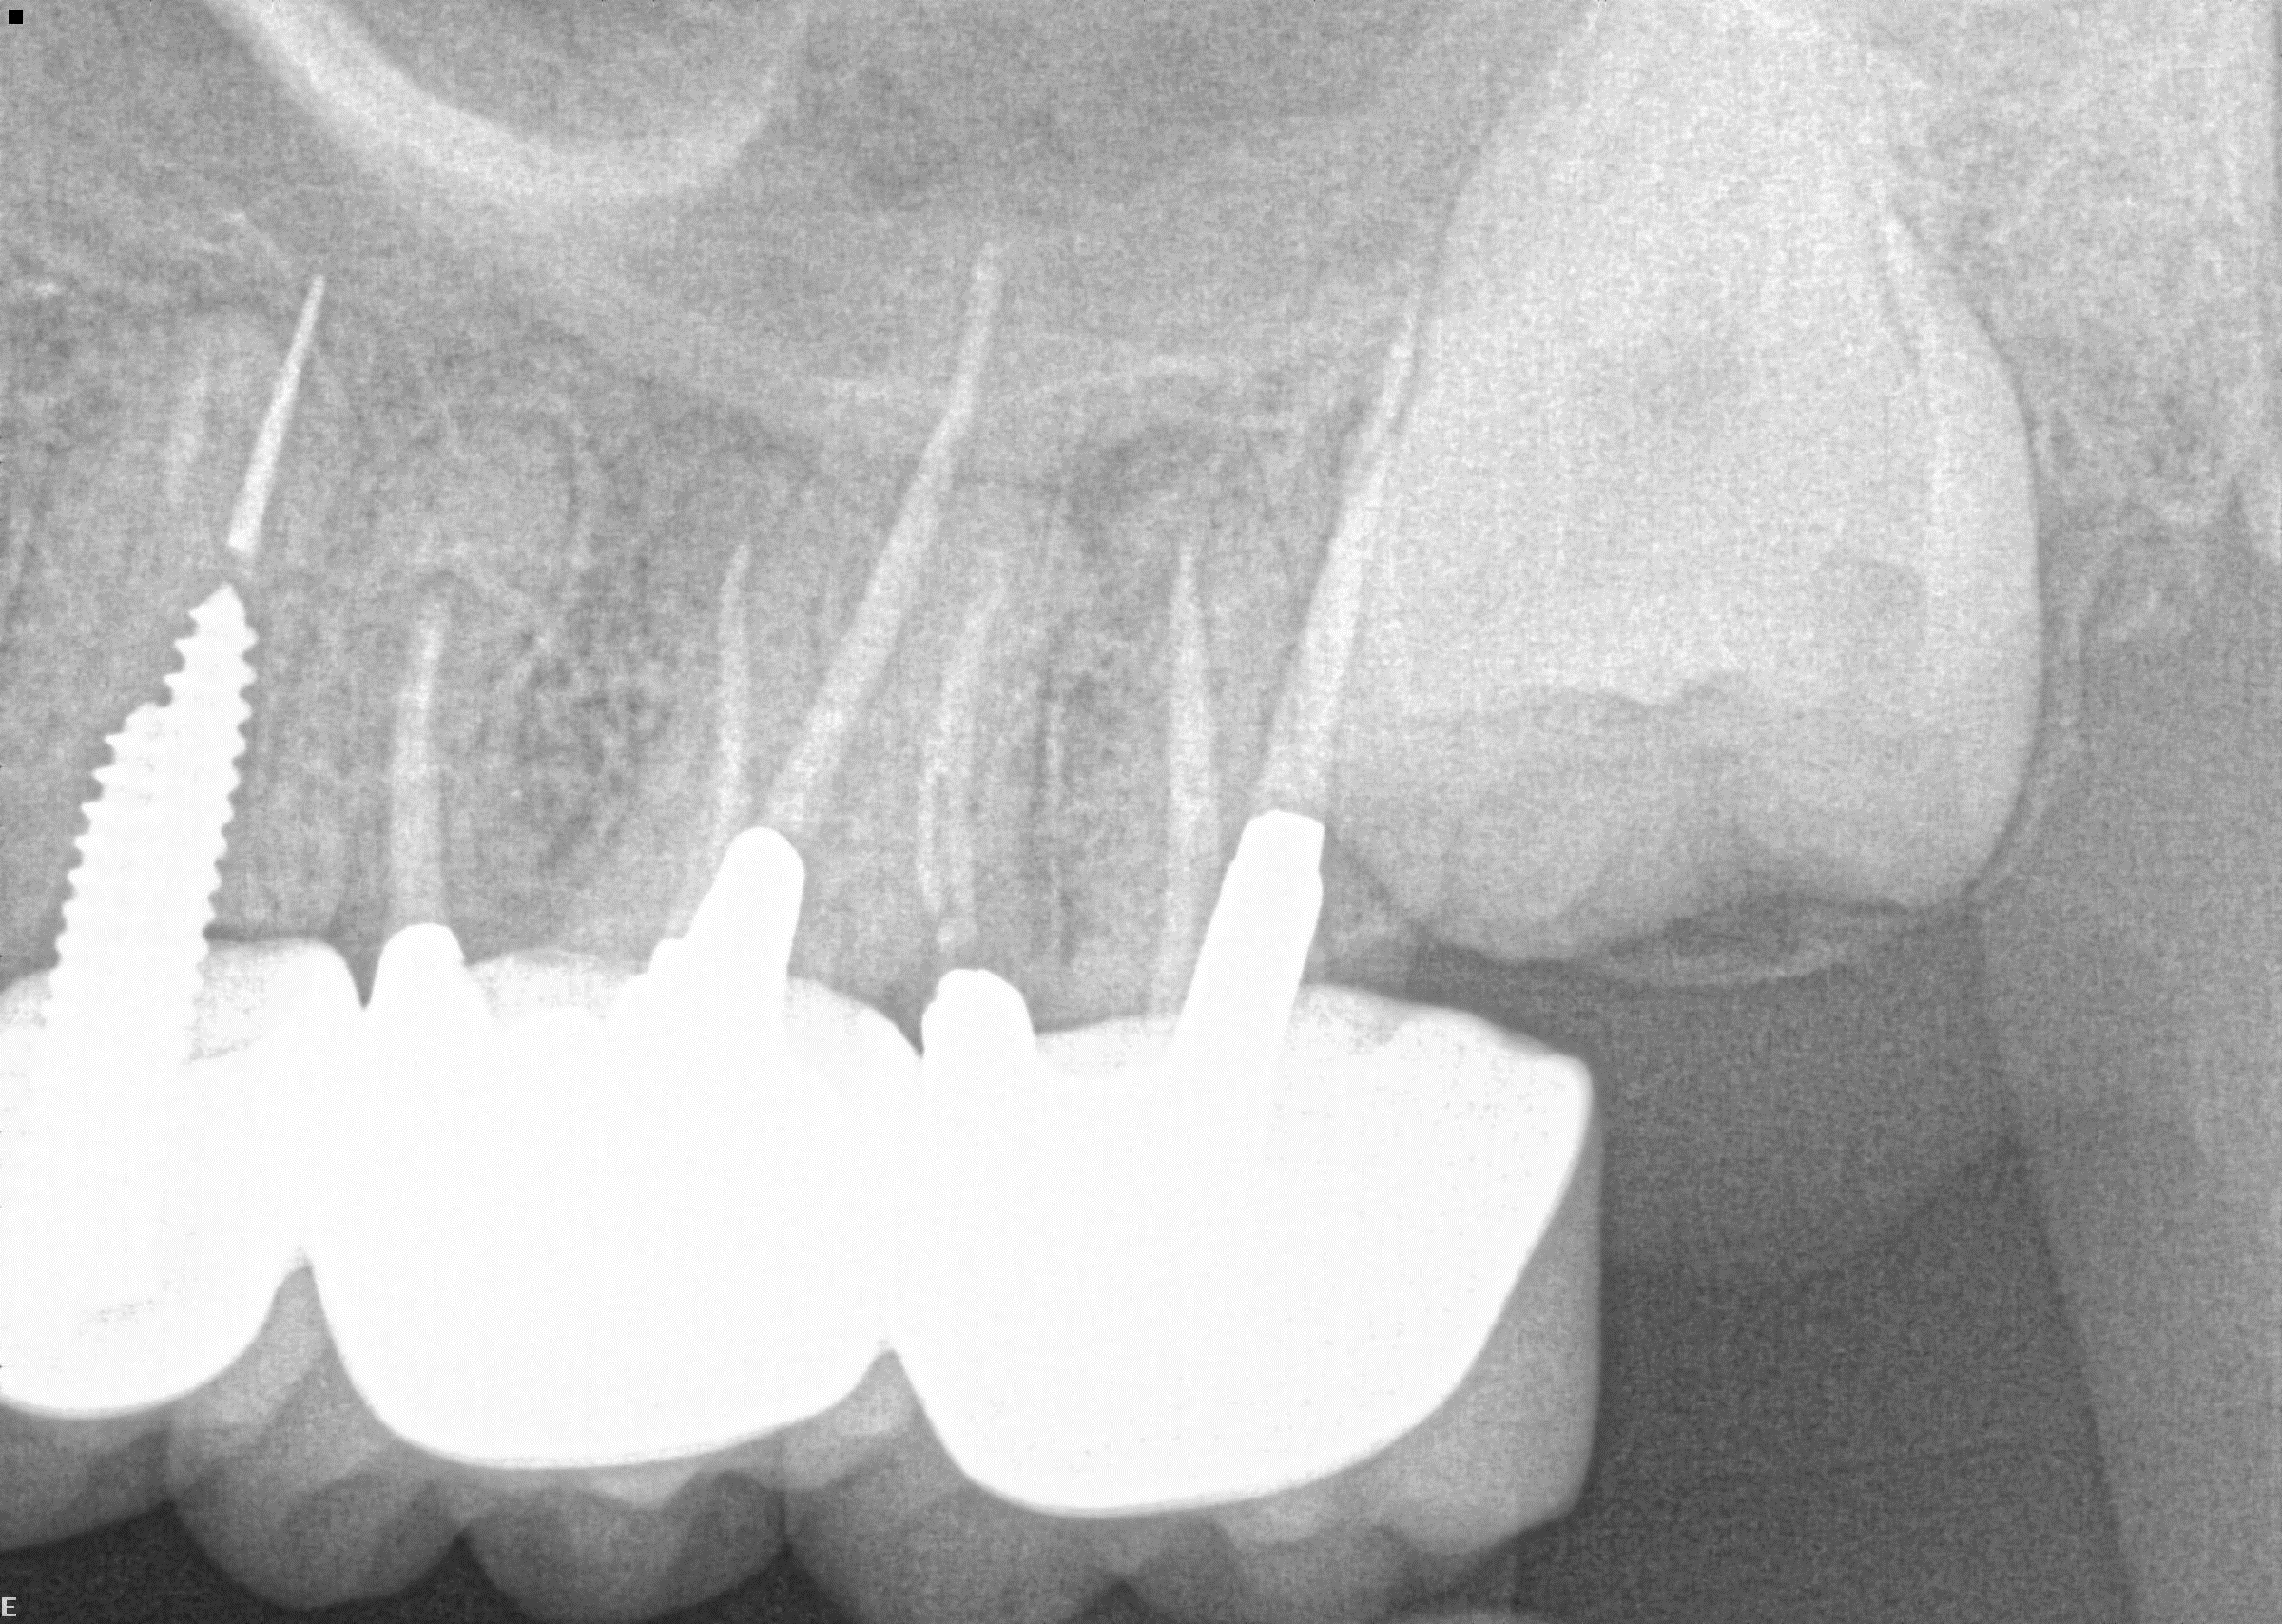

Tooth 4.8 is planned for extraction. Which radiographic findings suggest an increase in the degree of difficulty of the extraction?

13. (Select ONE OR MORE correct answers.)

Tooth 1.8 is planned for surgical extraction. Which radiographic findings suggest an increase in the degree of difficulty of the extraction?

Tooth 2.8 is planned for surgical extraction. Which radiographic findings suggest an increase in the degree of difficulty of the extraction?